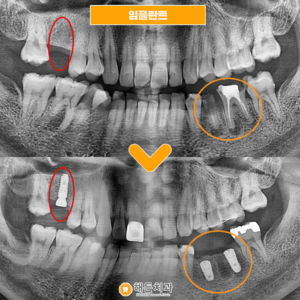

배방역치과 자연치아를 살리기 위해서는 (치료기간 : 2022.03~2022.06) 안녕하세요. 오늘은 저희 배방역치과를 내원하여 임플란트와 치관확장술을 통해 크라운치료하신 환자분을 소개해 드릴까 하는데요. 아래 사진을 보면서 설명해 드리도록 하겠습니다. 배방역치과 위 사진은 고*님의 치아 사진입니다. 고*님은 식사 때마다 통증을 느끼고 불편감을 느낀다고 하여 상담을 원한다고 하셔서 저희 치과에 내원해 주셨는데요, 더보기…